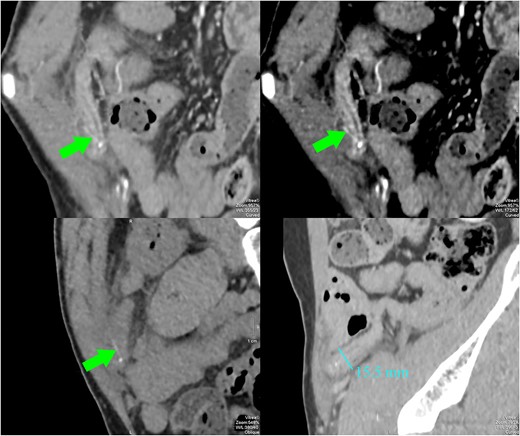

A 43-year-old man was hospitalized with dull pain in the right lower quadrant of the abdomen for 3 days. Accompanying symptoms were low-grade fever and nausea. In the emergency department, vital signs showed blood pressure 130/80 mmHg, heart rate 80 beats per minute, body temperature 37.9°C, and respiratory rate 22 per minute. Clinical examination revealed localized rebound tenderness on palpation at the right lower abdominal quadrant. Laboratory findings showed elevated white cell count of 15 000/mL (normal value <11 000/mL). Abdominal ultrasonography showed a large pus-filled appendix with an internal thin echogenic structure extending outward from the muscle layer and fatty infiltrates in the right iliac fossa (Fig. 1). In the ultrasound room, after being explained by the sonographer about the suspicion of appendicitis due to foreign bodies, the patient remembered and reported that he ate fish 5 days ago. CT scan performed then confirmed perforated appendicitis caused by a foreign body (Fig. 2). The patient underwent laparoscopic appendectomy without complications. The postoperative diagnosis was perforated appendicitis caused by fishbone (Fig. 3). The patient recovered and was discharged within 4 days.

CT images showed a dilated appendix (maximum diameter 15.5 mm) with thickened and hyperenhancing wall. A small amount of free fluid and fat stranding was seen in the right iliac fossa. There was a linear hyperdensity measuring 13 mm (arrows) perforating and extending slightly beyond the appendix. No abscess or free gas collection was detected.